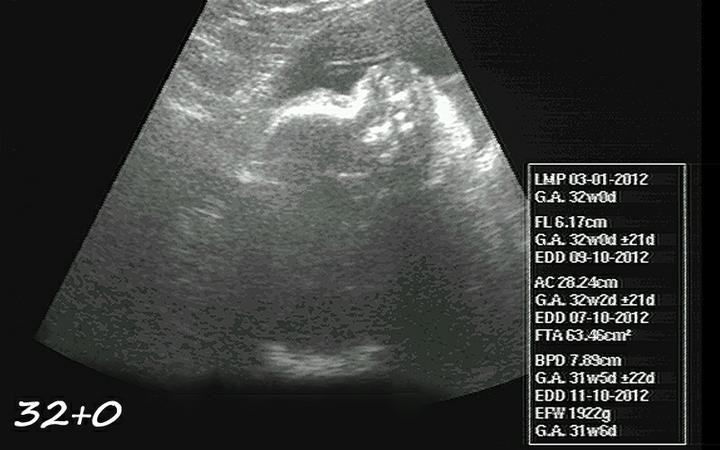

55 dní, začínám 33tt, miminko má cca 1930g po včerejším měření, je hlavičkou dolů. Jsem na tu naši druhou holčičku zvědavá, jestli bude podobná Niki nebo jiná. V noci už se moc nevyspím a po porodu to nebude lepší 🙂

začínám 30tt-24.7. ultrazvuk, malá je snad zdravoučká a už ted je to naše láska 🙂 má odhadem v 29+0tt 1357g, rozměry bříška a hlavičky odpovídají stáří, ale nožička je o týden delší. No prý to bude dlouhán, což mě pobavilo, protože Nikolka měla při narození jen 43cm ( 36+3tt ). Tak uvidíme, jestli budou sestřičky každá úplně jiná 🙂